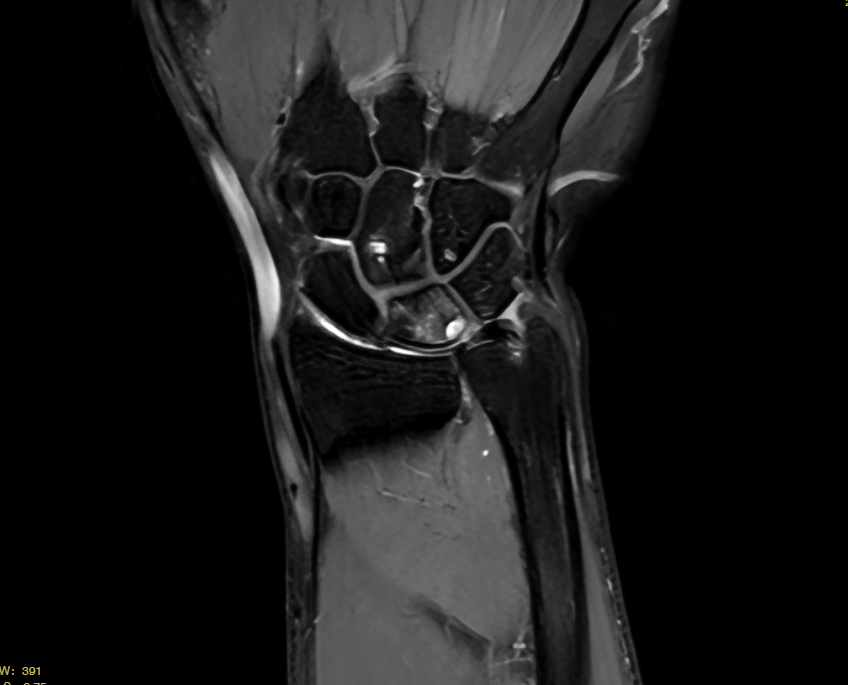

MRI示:月骨内可见囊性改变,TFCC 信号明显增高、连续性中断。